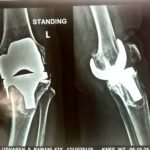

Revision knee replacement surgery is performed when a previously replaced knee joint develops problems such as pain, instability, stiffness, infection, implant loosening, or wear over time.

In this procedure, part or all of the existing knee implant is removed and replaced with new components to restore knee function and reduce pain.

Revision surgery is more complex than primary knee replacement and requires careful planning and expertise. The goal is to improve stability, alignment, and mobility of the knee, helping patients return to comfortable daily activities.